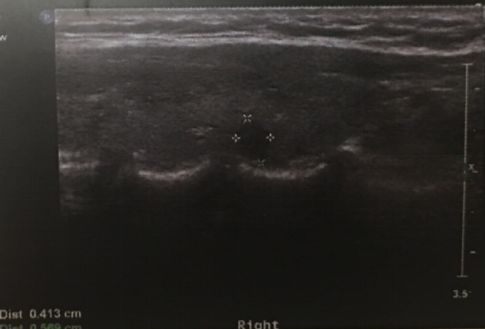

手术前诊断的金标准是细针穿刺活检(fine needle aspiration,FNA),但是对于肿瘤直径特别小(如小于5mm)的癌灶,可能并不适合穿刺,或者穿刺有假阴性可能或为意义不明确的结果。当超声检查发现典型的超声表现时,包括低回声、微钙化、纵横比大于1等,基本也可以诊断PTMC。临床诊断的建立同时要兼顾患者是否具有甲状腺癌的高危因素,如家族史,颈部放射史等。

图:超声发现直径4mm的PTMC。